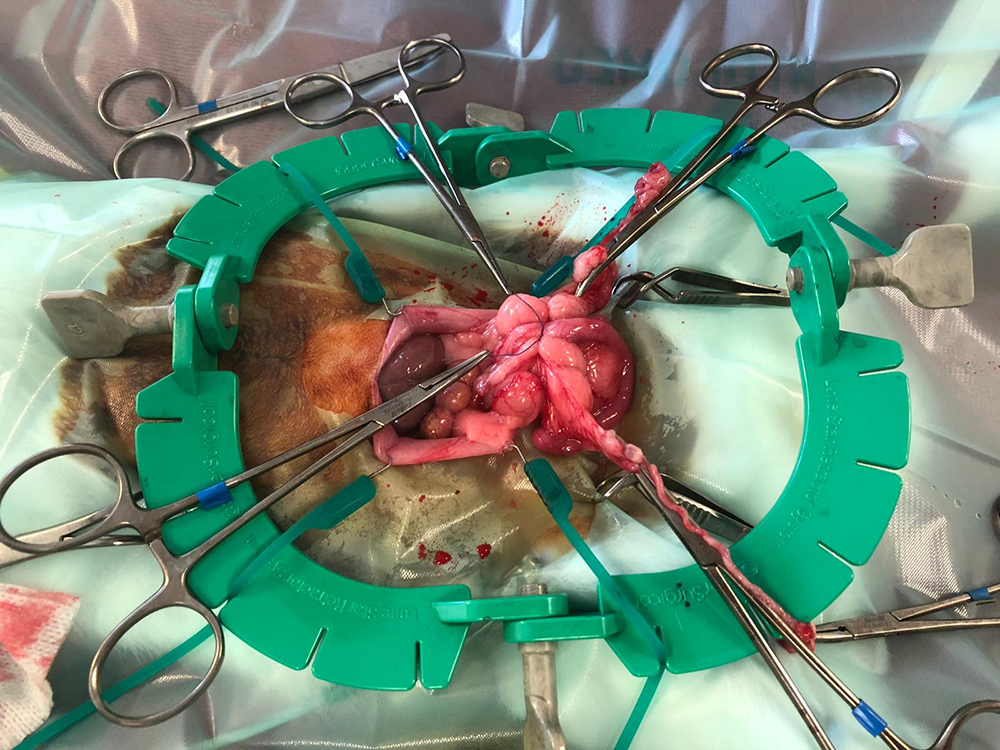

Nu kan de buik geopend worden, tot vlak voor het bekken. Om de buik open te houden, wordt de “lone star retractor” geplaatst. Hiermee is er goed zicht en werkruimte te verkrijgen. De eierstokken liggen bij het konijn vrij ver naar de zijkant, de darmen liggen vaak in de weg en zijn erg fragiel. Met de “lone star retractor” kan de sterilisatie veiliger worden uitgevoerd.

Na het afbinden van de bloedvaten worden de eierstokken en de baarmoeder verwijderd. Hierbij wordt goed opgelet dat ook daadwerkelijk de hele eierstok verwijderd wordt, wat soms lastig te zien is door het vet eromheen.

Hierna worden de buikwand, de onderhuid en de huid gesloten. Vaak is het weefsel heel dun waardoor het hechten lastig kan zijn. Het is zaak om de hechtingen goed onder de huid te krijgen.